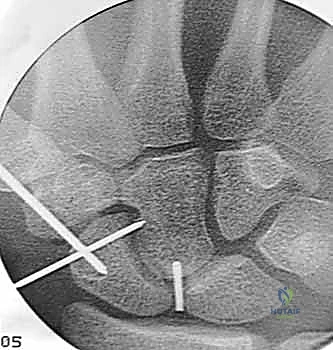

هذه هي التقنية المتقدمة التي يبرع فيها الأستاذ الدكتور محمد هطيف في صنعاء. بدلاً من فتح الرسغ، يتم إجراء العملية بأكملها من خلال شقوق دقيقة لا تتجاوز 2-3 مليمترات، تحت إرشاد جهاز الأشعة المرئية (Fluoroscopy) وبمساعدة المنظار المفصلي الدقيق.

العملية الجراحية بتقنية التدخل المحدود ليست مجرد "إدخال مسمار"، بل هي عمل فني وهندسي دقيق يتطلب مهارة جراحية فائقة، تخطيطاً مسبقاً، وتنسيقاً مثالياً بين يدي الجراح والصور الإشعاعية. يتبع الأستاذ الدكتور محمد هطيف بروتوكولاً صارماً لضمان أعلى معدلات النجاح.